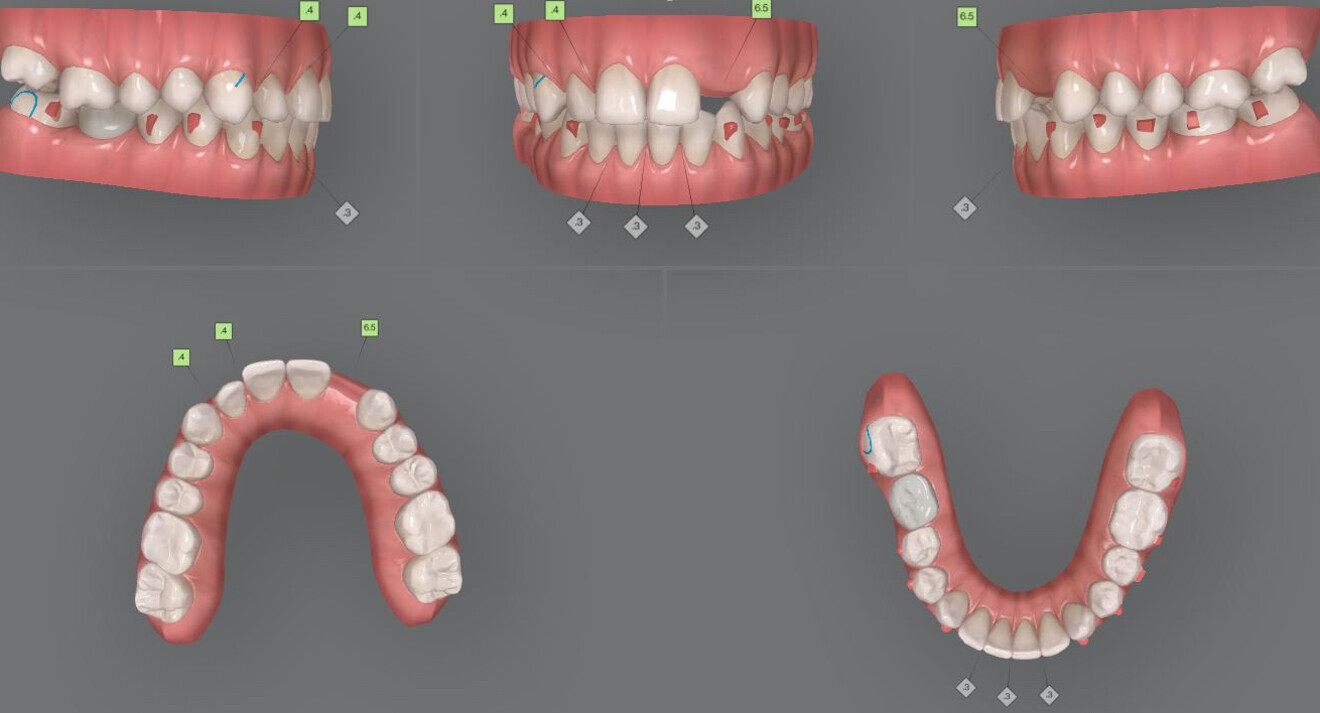

Fig. 8: Additional aligners ordered.

Since the patient was living abroad and close monitoring was not possible, some mid-treatment corrections were necessary (Fig. 6). During treatment, the following issues arose: poor posterior occlusion during the distalisation process and tipping of tooth #21 (Fig. 7). The latter was caused by the lack of an attachment on this tooth in the initial treatment plan. These issues were addressed in the additional aligner order with torque control and extrusion of posterior teeth to establish good posterior occlusal contacts and with the use of optimised root control attachments to correct the angulation of the maxillary central incisors (Fig. 8).